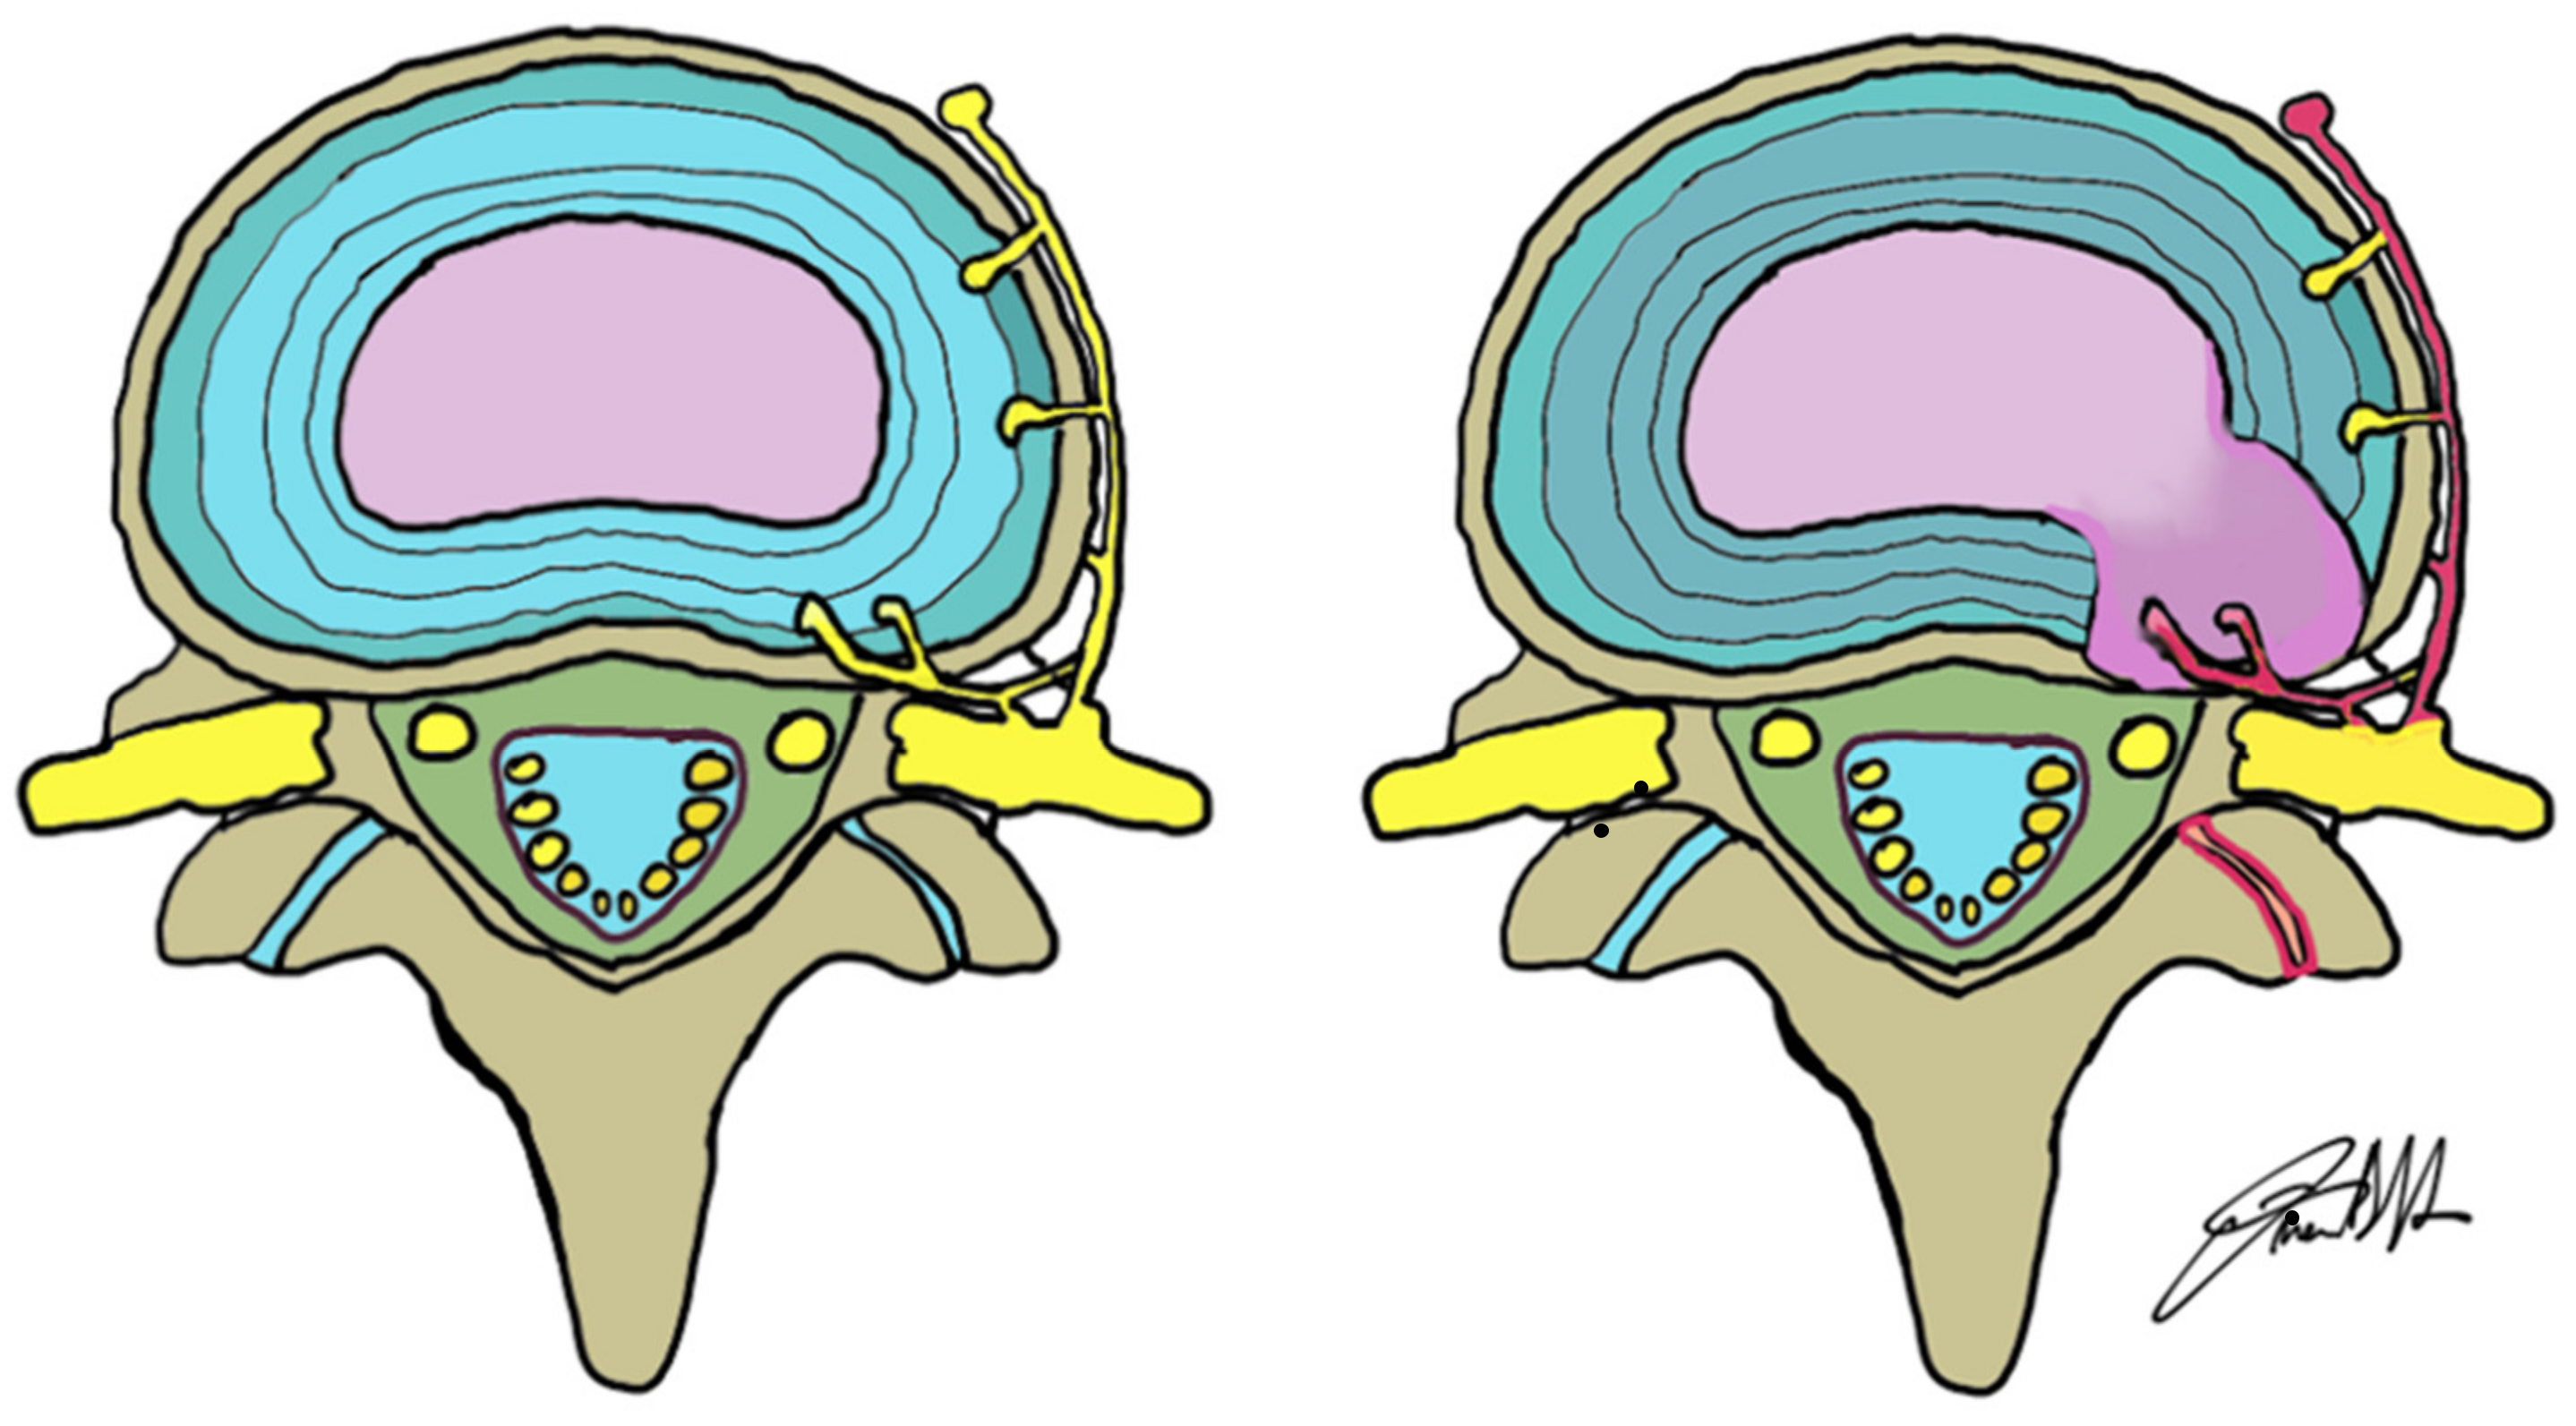

- Freemont, A.; Peacock, T.; Goupille, P.; Hoyland, J.; O’Brien, J.; Jayson, M. Nerve ingrowth into diseased intervertebral disc in chronic back pain. Lancet 1997, 350, 178–181. [Google Scholar] [CrossRef]

- Kim, H.S.; Wu, P.H.; Jang, I.-T. Lumbar Degenerative Disease Part 1: Anatomy and Pathophysiology of Intervertebral Discogenic Pain and Radiofrequency Ablation of Basivertebral and Sinuvertebral Nerve Treatment for Chronic Discogenic Back Pain: A Prospective Case Series and Review of Literature. Int. J. Mol. Sci. 2020, 21, 1483. [Google Scholar] [CrossRef]

- Ohtori, S.; Miyagi, M.; Inoue, G. Sensory nerve ingrowth, cytokines, and instability of discogenic low back pain: A review. Spine Surg. Relat. Res. 2018, 2, 11–17. [Google Scholar] [CrossRef]

- Lama, P.; Le Maitre, C.L.; Harding, I.J.; Dolan, P.; Adams, M.A. Nerves and blood vessels in degenerated intervertebral discs are confined to physically disrupted tissue. J. Anat. 2018, 233, 86–97. [Google Scholar] [CrossRef]